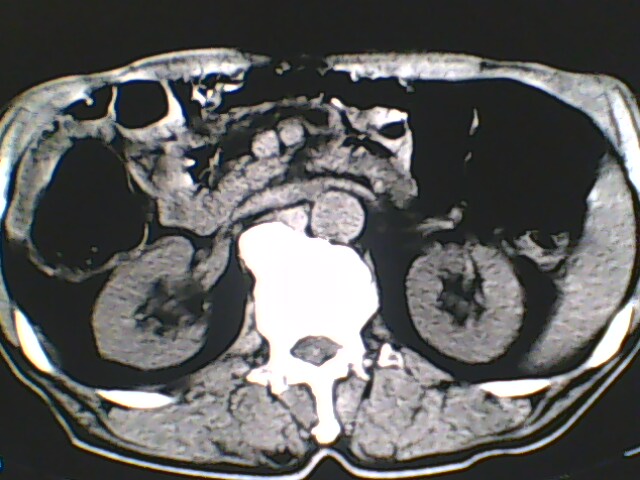

男,56岁,高血压,临床怀疑肾上腺问题,肝脏怎么那么高啊?能描述一下么?

右侧膈膨升,间位结肠,胸腰椎退行性骨关节病,右侧肾上腺可疑增生(图像颗粒太粗,窗太窄,不好看)。

支持 右侧膈膨升,间位结肠;胸腰椎退行性骨关节病;双侧肾上腺可疑增生。